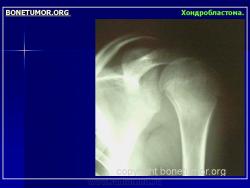

Рентгенологически хондробластома представляет собой сравнительно большой (2-4 см) очаг округлой формы, четко отграниченный от окружающей кости склеротической каймой. На фоне очага в большинстве случаев, но не обязательно определяются плотные включения, напоминающие хлопья ваты.

Рентгенологическая картина. Хондробластома выглядит как небольшой, от 3 до 6 см литический очаг, центрально или эксцентрично расположенный, с четкими контурами, занимающий около половины площади эпифизарной зоны. Хондробластома плоских костей и мелких трубчатых костей больших размеров, может сопровождаться припухлостью мягких тканей, вздутием кости и периостальной реакцией. Распространение процесса на метафизарную зону встречается часто.

Fig. 19. Chondrobastoma: An expansile lesion involving theepiphysis, physis and metaphysis of the humerus is depicted. The lucent lesion shows cortex destruction and spotty matrix calcifications.